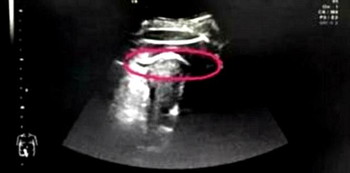

Pakar mengesyaki rahim Zhang telah pecah lalu mereka melakukan imbasan ultrasound untuk mengesahkannya.

Dari imbasan ultrasound itu, doktor terkejut mendapati bayi tersebut telah menendang rahim ibu dengan terlalu kuat hingga kakinya terjulur keluar dari dinding rahim.

Kaki bayi tersebut kini berada di rongga abdomen ibu dan tidak keluar sepenuhnya kerana tersekat pada bahagian paha.